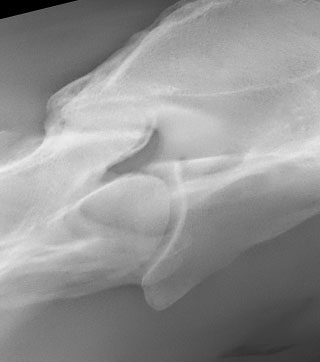

Radiología

Contamos con el equipo de radiología digital inalámbrico más avanzado del país, el cual permite obtener las mejores imágenes en el acto y compartirlas vía mail. Realiza radiografías de miembros, columna, cabeza, cuello y hombro.